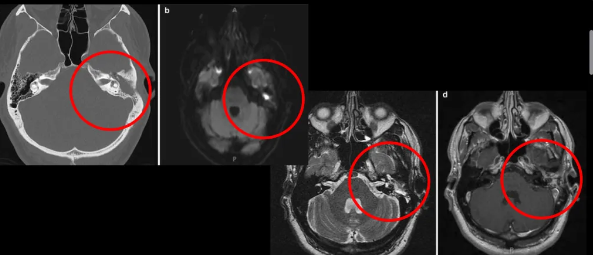

Cuál es tu diagnóstico?

Otitis media

Dx de la siguiente imagen

Mastoiditis

De que enfermedad se trata y qué complicacion está presentando

Mastoiditis con invasión a SNC con un absceso que provoca una meningitis